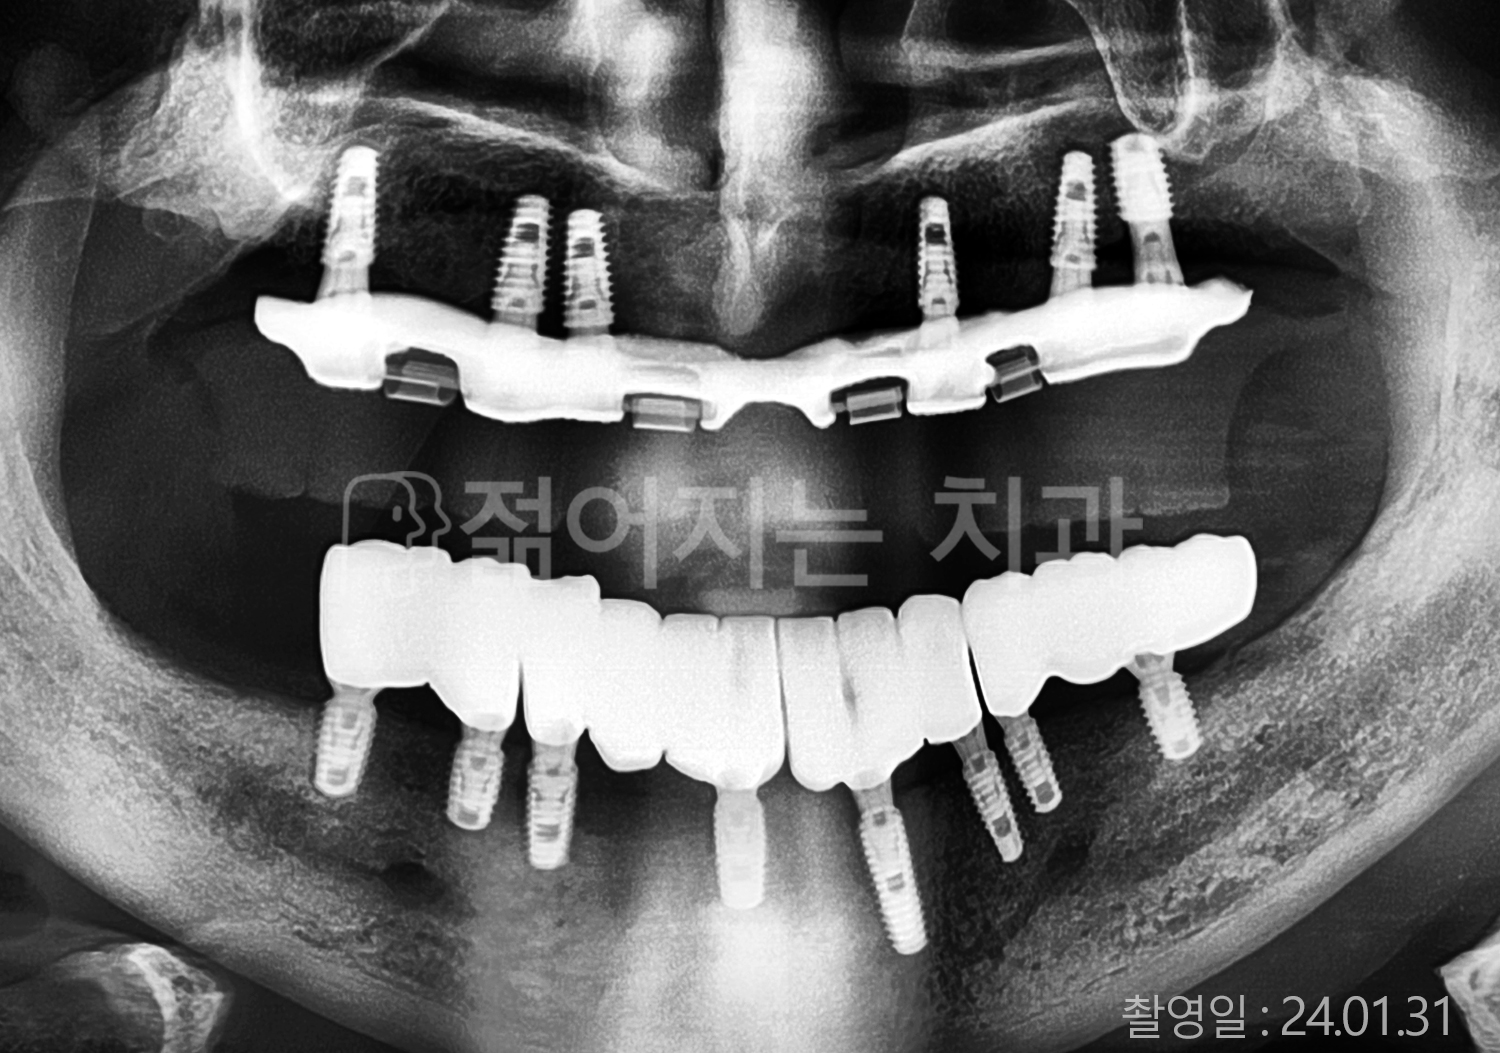

• 60대 고혈압, 고지혈증 전체치아 10개 이상 임플란트

• 70대 전체치아 10개 이상 임플란트

• 60대 전체치아 10개 이상 임플란트

• 50대 전체치아 10개 이상 임플란트

• 50대 고혈압, 고지혈증 전체치아 10개 이상 임플란트

• 60대 고혈압, 당뇨, 고지혈증 전체치아 10개 이상 임플란트

• 80대 고혈압, 당뇨, 골다공증 전체치아 10개 이상 임플란트

• 60대 고혈압 전체치아 10개 이상 임플란트

• 60대 고지혈증 전체치아 10개 이상 임플란트

• 60대 당뇨 전체치아 10개 이상 임플란트